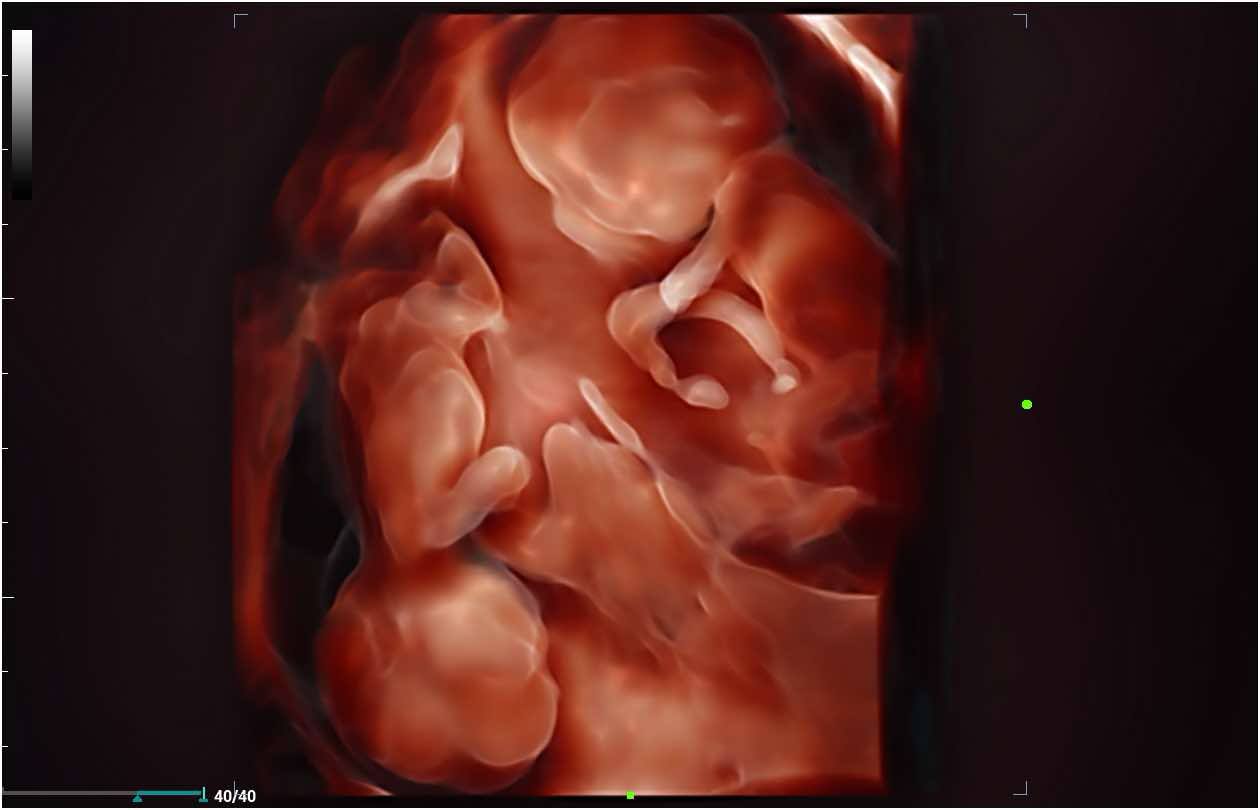

The birth of a new baby is an exciting time for parents, family and friends! At Bonding Moments, we offer a warm family atmosphere that offers Elective 2D/3D/4D and HD prenatal ultrasounds. We use state of the art ultrasound technology that allows our trained technicians to bring your baby to life before your very eyes on an 86 in flat screen TV surrounded by up to 12 of your guests. The realistic images will provide a bonding experience between mommy, daddy, family and friends. See baby yawn, hiccup, smile and kick all in real-time. So, let’s take a journey together and peek inside your baby’s world!

A prenatal ultrasound uses a transducer to deliver high frequency sound waves. Echoes of the sound waves are recorded and transformed into pictures. A gel is applied to the belly and transducer before the scan which helps conduct the sound waves. 2D and 3D are still images .4D adds motion and dimension so it looks like a video and HD adds more realism.